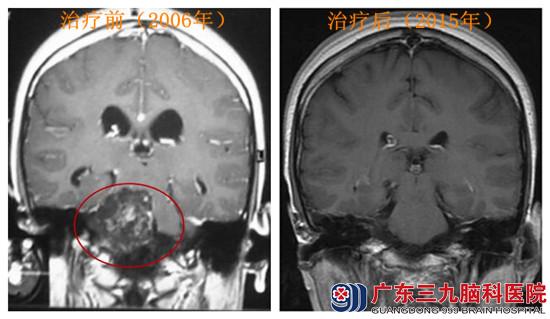

林某,女性,18岁。2006年9月下旬因无明显诱因出现头晕,伴轻度头痛,恶心伴视物不清15天,于当地医院就诊。行CT检查提示:蝶鞍区占位病变,建议MR检查,为进一步诊治,患者来到广东三九脑科医院,行MR检查提示:鞍背及斜坡后方占位性病变,考虑脊索瘤可能性大,拟“鞍背及斜坡后方占位性病变”收入院。起病以来,患者一般情况好,精神佳,大小便正常。

治疗:于当年10月行斜坡占位性病变切除术,肿瘤大部分被切除,术程顺利,术后病理明确为:脊索瘤。恢复后定位行头部放疗,2Gy/f,完成54Gy。

跟踪:患者定期复查未见肿瘤复发,目前已随访8年余,患者未再出现不适症状,并已经生育两个小孩。